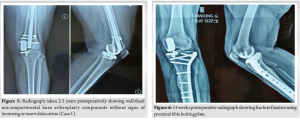

Two and a half months post-UKA, in December 2022, she was involved in a high-velocity road traffic accident. Radiographs revealed a proximal third tibial shaft PPF, classified as Type C according to the UCS. There was no evidence of ligamentous laxity. Both UKA components were well-fixed, and no insert dislocation was observed radiographically. The patient underwent internal fixation with a proximal tibial plate. Intraoperatively, the fracture line was found approximately 5 cm below the tibial component. Through an anterolateral approach, a long lateral anatomical plate was applied and fixed with locking screws. Her pre-injury OKS was 46. Following fixation, it decreased to 32. Active-assisted and passive knee range-of-motion exercises were initiated immediately. At 14 weeks postoperatively, radiographs and computed tomography scans demonstrated good fracture union (Fig. 6), and full weight-bearing was permitted. Her OKS had improved to 38.

By 6 months, she had regained full range of motion (130°), could sit cross-legged, and walked independently without aids (Fig. 7 and 8). At 2 years and 8 months from the primary UKA (2 years and 5 months post-fracture fixation), the UKA components remained well-fixed, and her OKS was 46 (Fig. 9).